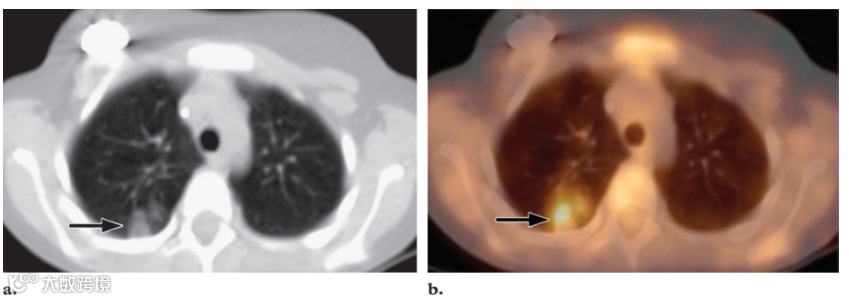

局部FDG蓄积增多见于各种感染或炎症过程,包括脓肿、肺炎、鼻窦炎、骨髓炎、假体关节感染、结核病、传染性单核细胞增多症以及真菌或肉芽肿性疾病,如曲霉病、隐球菌病、组织胞浆菌病、结核病、韦格纳肉芽肿病、组织细胞增生症和结节病。如前所述,据报道,患有炎症性肠病的儿童会出现FDG摄取。肺炎可能表现为肺部局部摄取明显增加,通常在抗生素治疗后消退(图18)。臀部肌肉中FDG的聚集灶强烈提示注射部位肉芽肿,尤其是近期有肌肉注射史的患者。反复将药物注射到皮下脂肪后,也会发现注射部位肉芽肿。接受低分子量肝素皮下注射的患者可能会在注射部位出现FDG亲和的软组织衰减皮下区域。此类结节在CT上可能类似于转移性肿瘤沉积物。这些病变内炎症细胞和巨噬细胞的积聚可能解释了病变内FDG的积聚。需要与临床病史仔细对照,以避免误诊(图19)。活动性血管炎症可能显示FDG摄取。FDG PET/CT 图像可以帮助检测大动脉炎并反映血管壁炎症活动的分布。

图18. 一名8岁男孩的肺炎,他有神经母细胞瘤病史,发烧和咳嗽。

(a)轴位CT扫描(肺窗)显示右肺感染区域(箭头)。

(b)轴位融合FDG PET/CT 图像显示右肺摄取明显增加(箭头),这一发现与感染区域相对应。在抗生素治疗后进行的随访成像中,感染已消退。